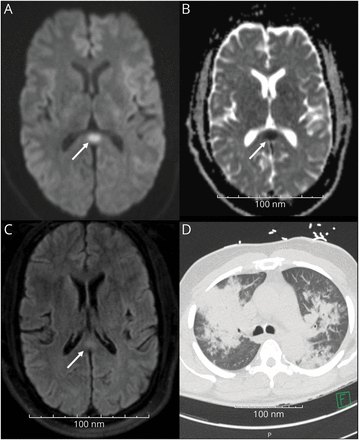

图 大脑MRI和CT胸部

(一)diffusion-weighted核磁共振成像系列的轴向定位。箭头指向的焦点hyperintensity在中线的胼胝体压部。(B)轴向取向与表观扩散系数关联在CC中线压部如箭头所示。(C) T2 fluid-attenuated反转恢复MRI显示hyperintensity CC的位置。(D) CT胸部没有第四密度对比展示consolidative双边肺透明。

动脉血气透露一个阴离子间隙酸中毒二级乳酸酸中毒。15.7他白细胞增多,肾和肝脏功能障碍的证据。CT胸部已经完成了密集的两国合并(图)。他快速的冠状病毒疾病2019 (COVID-19)测试是负面的。核磁共振大脑没有限制扩散的对比表现出小关注CC中线与表观扩散系数匹配压部(图与细胞毒性损伤)一致。没有发现其他异常轴向diffusion-weighted 41,梯度回波,T2 fluid-attenuated反转恢复(天赋)图像。由于血管事件的典型位置,这个假定可逆细胞毒性损伤的CC促使进一步感染引起败血症的设置。研究包括血培养、艾滋病、军团菌、细小病毒B19,巨细胞病毒,巴尔病毒,流感和呼吸道面板测试A和B,腺病毒、副流感病毒、肺炎支原体。